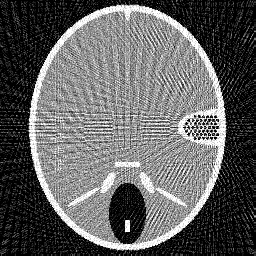

Figure 2. Results of different methods for reconstructing the head phantom with underdetermined rate 25% and relative noise level 0.2. (a) FBP (SNR=0.3253), (b) Landweber (SNR=0.1718), (c) Kaczmarz (SNR=0.1406), (d) L2-TV with scalar λ𝜆\lambda (SNR=0.0644), (e) Our method (SNR=0.0525), (f) λ𝜆\lambda in our method.

Figure 3. Results of different methods for reconstructing the head phantom with underdetermined rate 25% and relative noise level 0.8. (a) FBP (SNR=0.3505), (b) Landweber (SNR=0.1740), (c) Kaczmarz (SNR=0.1448), (d) L2-TV with scalar λ𝜆\lambda (SNR=0.1072), (e) Our method (SNR=0.0762), (f) λ𝜆\lambda in our method.

In Figure 2 and 3, we give the reconstruction results, which are shown in the same intensity range as the original phantom, from the simulated measurements with the noise level 0.2 and 0.8, respectively. Since the FBP algorithm is according to the analytical formulation of the inverse X-ray transform, it implicitly requires to have continuously measured clean data from the whole 0 to π𝜋\pi angular range. Therefore, it is not suited for reconstructing from noisy limited data. We can clearly see many stripe artifacts due to the noise and sparse projection angles in the FBP results. Both the Landweber and Kaczmarz’s methods perform better than FBP, but there are still some visible artifacts in the reconstruction. By using the TV regularization in the L2-TV and our methods, we potentially assume that the reconstructions are piecewise constant, which evidently reduces the influence of the noise and avoids stripe artifacts. In addition, comparing the results from the L2-TV and our methods, we find that our method suppresses artifacts much better while reconstructing most details. For instance, the grey region in the head and the black dotted region on the right side. With respect to SNR, it is also clear that our method gives the best reconstruction results. In Figure 2 (f) and Figure 3(f), we also plot the λ𝜆\lambda function obtained by our method. One can see that in the more textured regions λ𝜆\lambda is large in order to preserve the details, and in the more homogenous regions it is small to reduce artifacts.